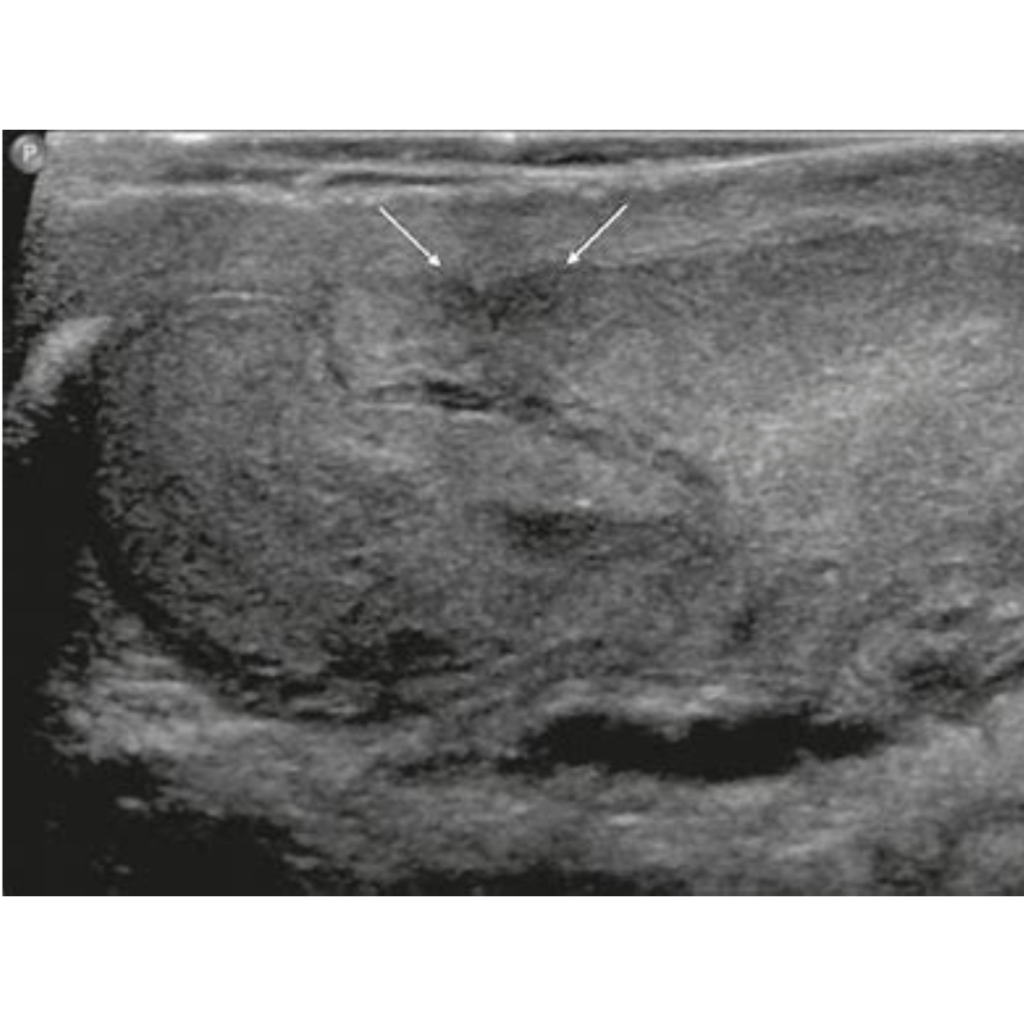

A testicular ultrasound is a non-invasive procedure that uses sound waves to create images of the testicles and surrounding structures in the scrotum. It is used to evaluate testicular masses, pain, swelling, or trauma.